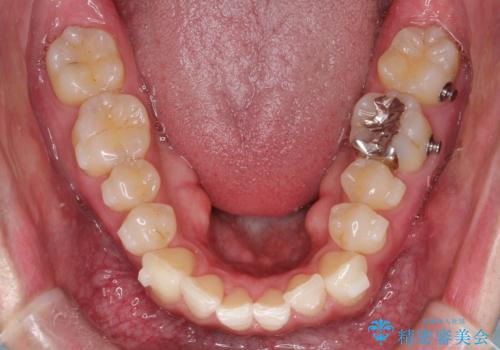

- 前歯の凸凹と顎の偏位を主訴に来院されました。

下顎の偏位を認めましたが、外科矯正を希望されなかったためできる範囲で顎の偏位を治すことができるよう治療を行なっております。

治療開始前に、下顎位の評価をおこなうことで、完成度の高い治療を行うことができました。